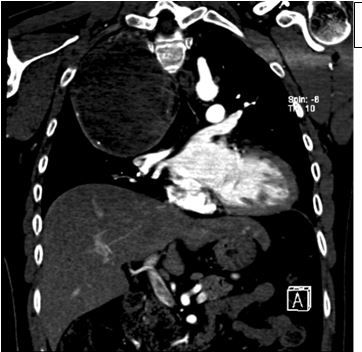

Figure 3. CT of the chest, coronal view.

A 35-year-old man with no significant past medical history, presents to the emergency department (ED) with worsening right shoulder pain. He reports that he fell on the ice and injured the right chest wall and right shoulder, 2 weeks before presentation. He states that his pain has been worsening at the site of injury. The pain is relieved with NSAIDs. He reports that just recently he has begun to feel numbness and tingling in the third, fourth, and fifth finger digits bilaterally. He denies head trauma. He also denies any fevers, chills, weight loss, or sick contacts. He has no dyspnea or cough and has no recent travel history. The patient is a nonsmoker, works as a school teacher, and denies any occupational exposures.

The images shown in Figures 1-4 were obtained in the ED; there were no prior images for comparison.